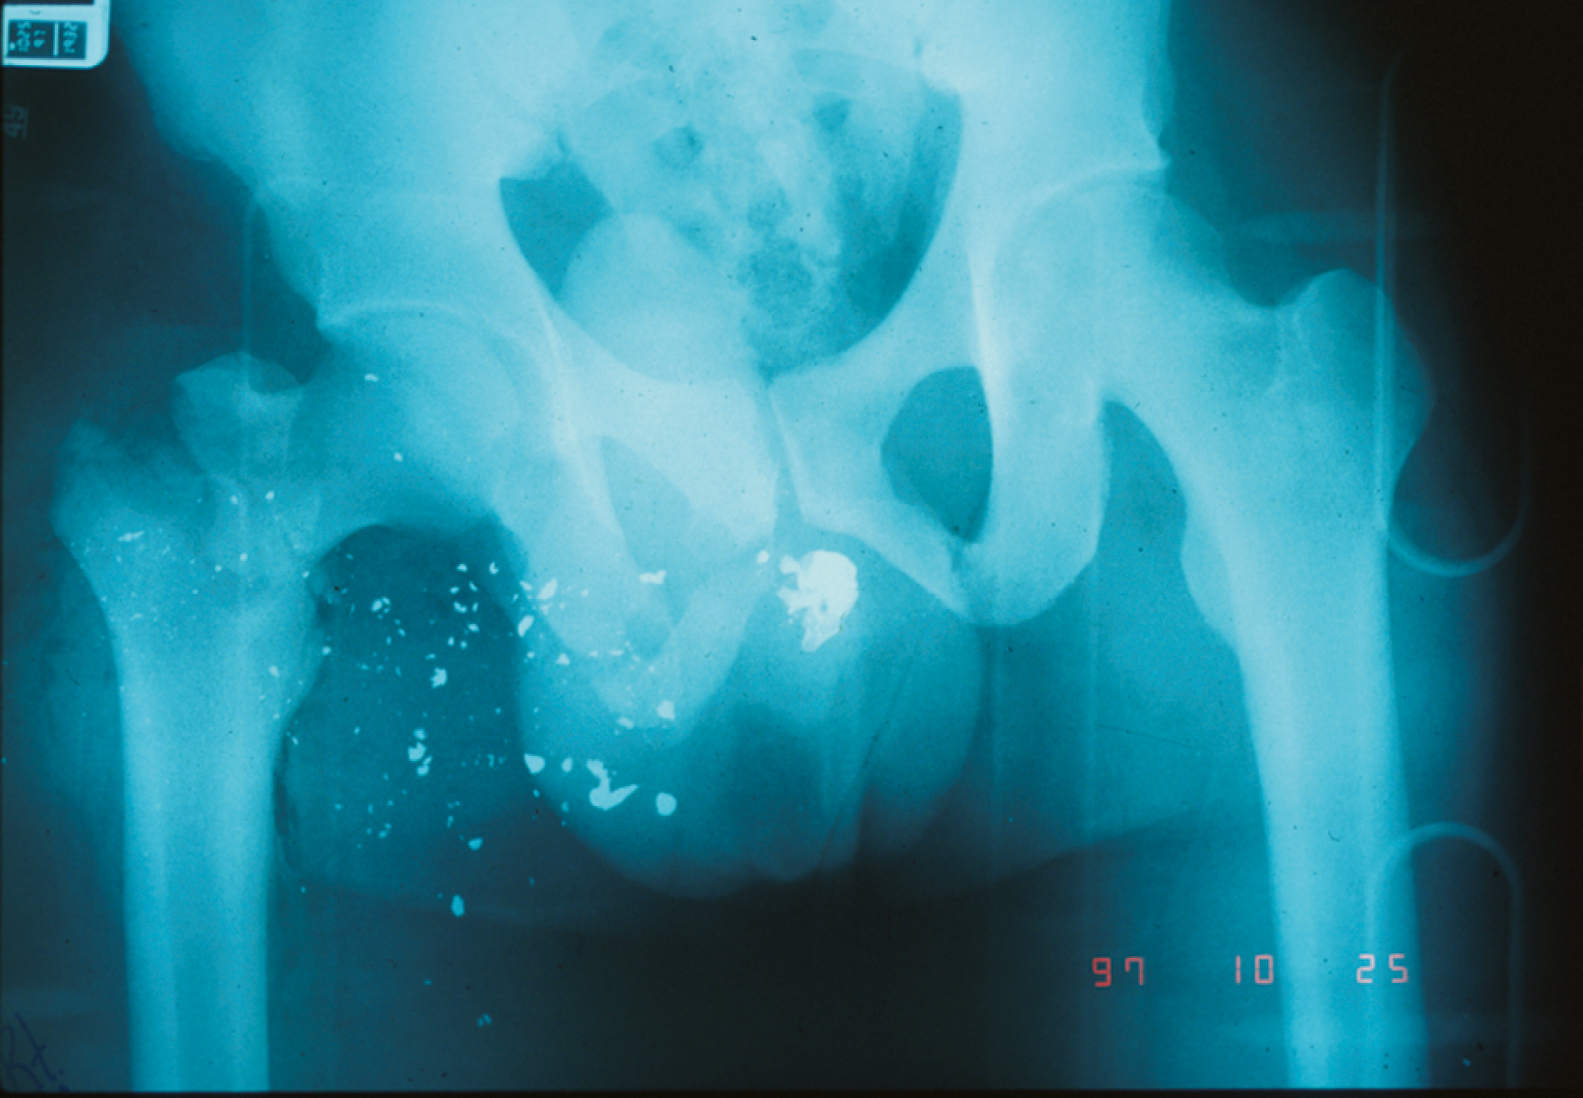

High-velocity bullets with jackets and lead cores generally break up into hundreds of fragments, termed a lead snowstorm , on entering tissue, resulting in significant tissue damage ( Fig. e11.15 ). If the tissue penetrated is deep, the bullet fragments may fail to exit and remain embedded. It is therefore possible to sustain an injury from a high-velocity round and not exhibit an exit wound. High-velocity rounds with steel cores will almost uniformly exit intact. Steel core ammunition is not available for civilian use so such injuries will rarely be encountered by most ED providers.

A lead snowstorm from a high-velocity rifle round. High-velocity projectiles have a tendency to fragment into hundreds of tiny particles on contact with bone. This fragmentation contributes to the massive tissue damage associated with these projectiles.